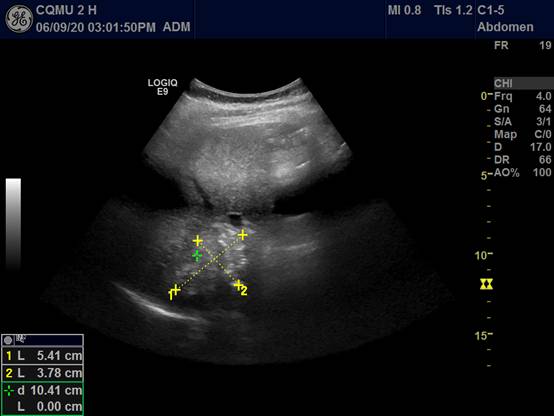

3.达到指定靶标后行消融治疗: